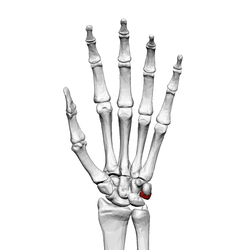

Left hand anterior view (palmar view). Triquetral bone shown in red.